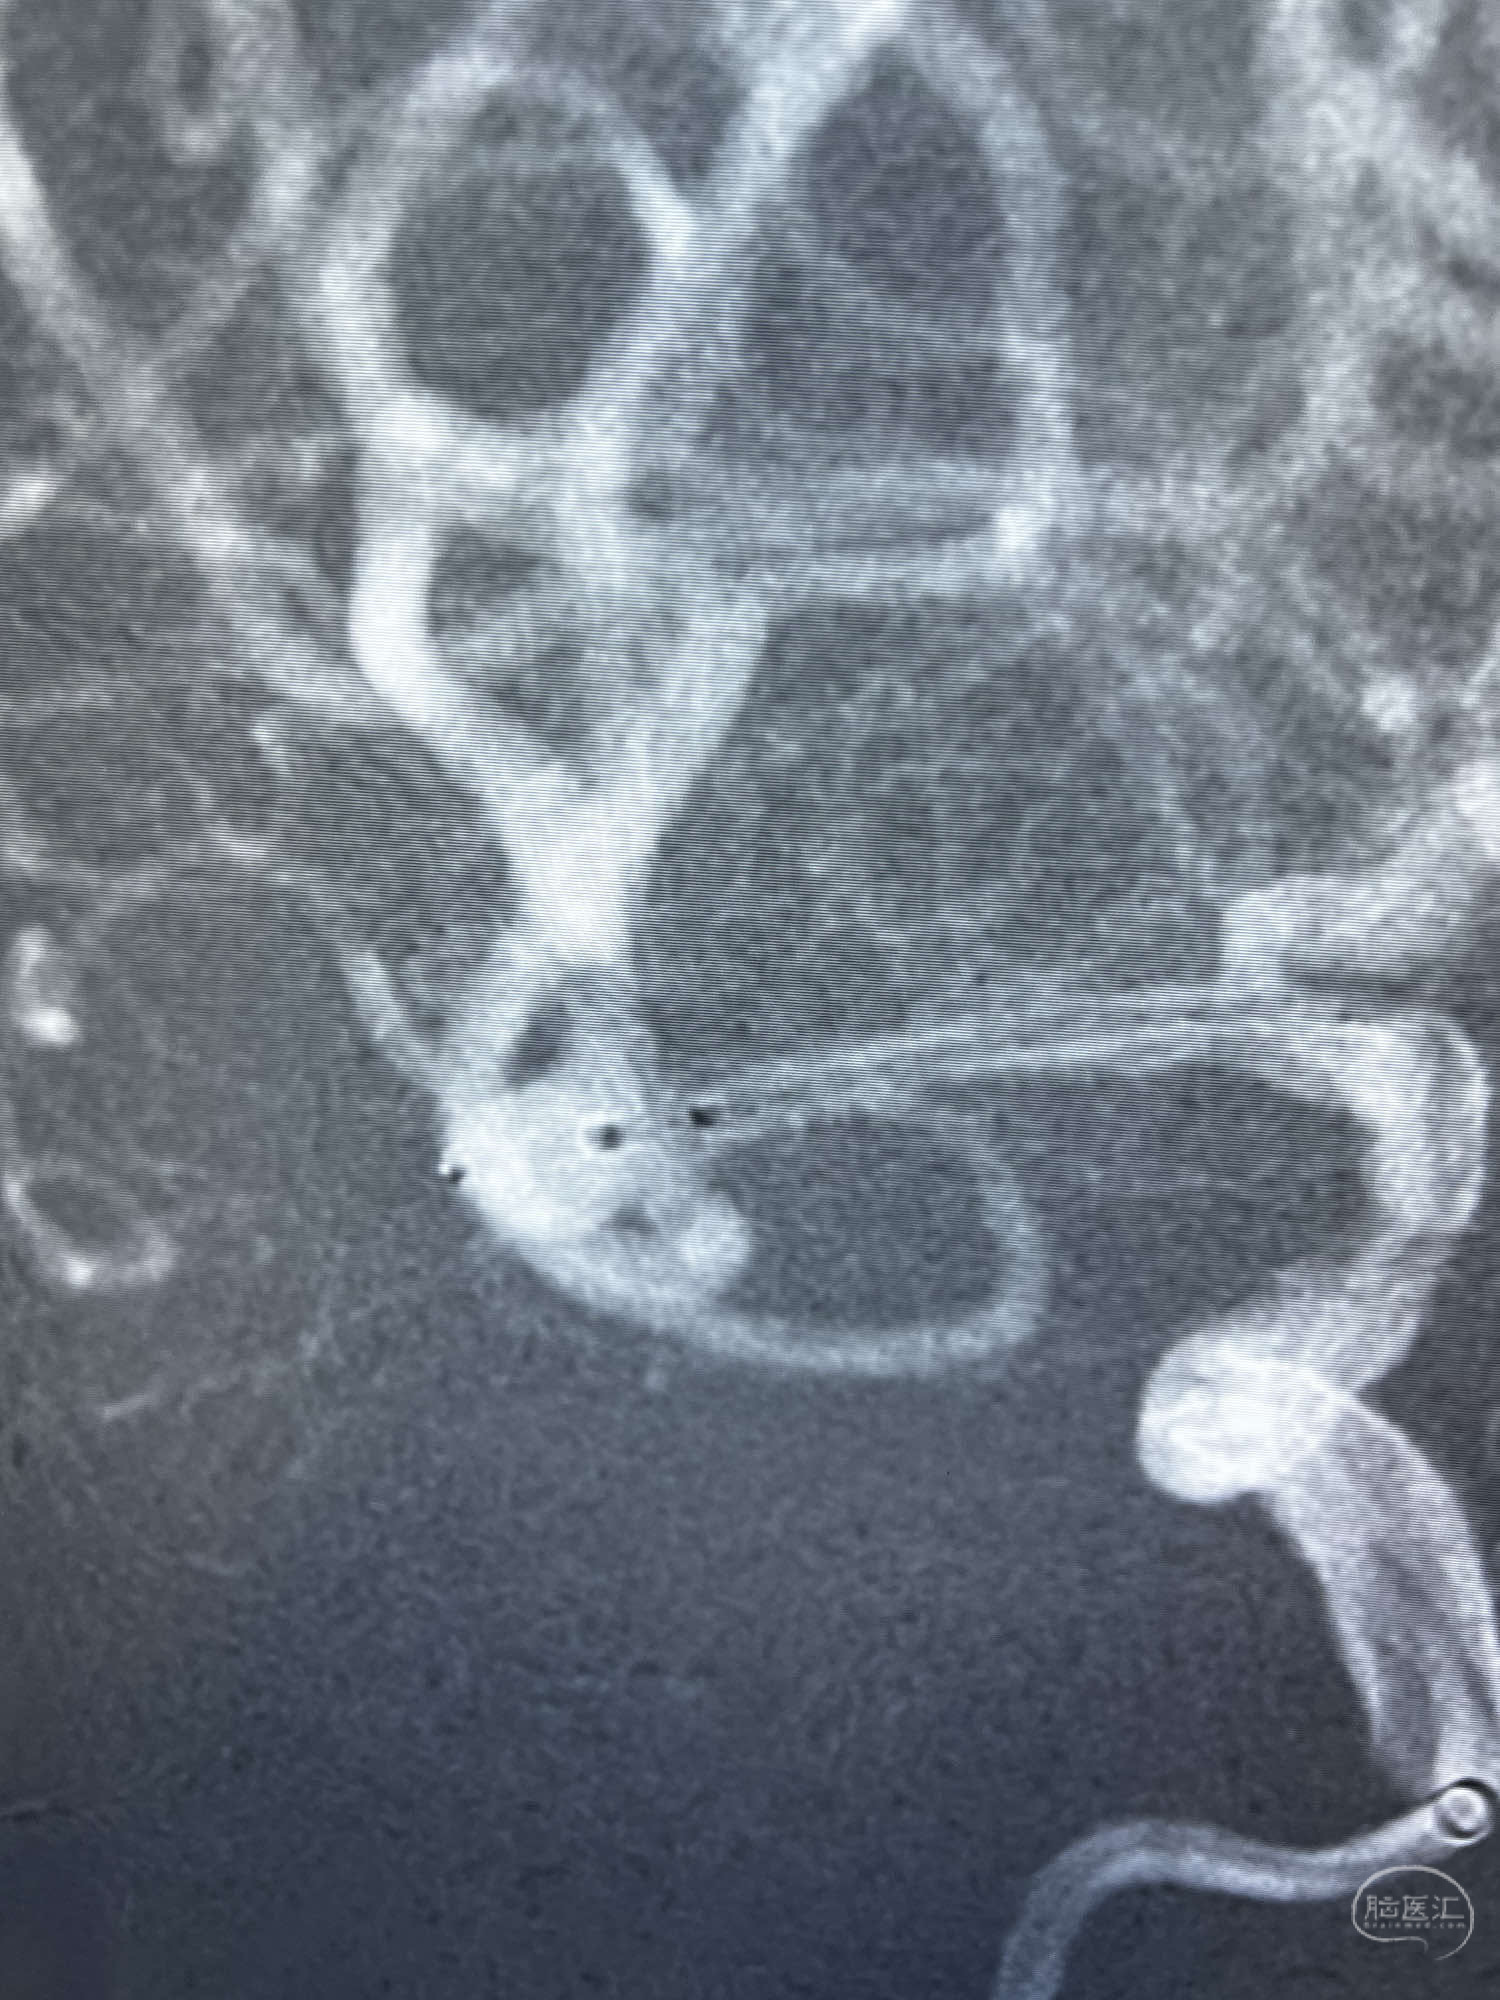

DSA示:左侧颈内动脉眼动脉段以远闭塞,后交通动脉开放,椎基底动脉通过后交通动脉代偿左侧大脑中动脉区域,右侧发出双侧大脑前动脉,右侧大脑中动脉M1末端宽颈动脉瘤,大小约4.3mmx4.6mm。

6F Neuromax➕6F115cm 心玮中间导管建立路径,sychro14微导丝➕VIA21超选至动脉瘤体内近中部,WEB5mmx3mm植入动脉瘤。

WEB瘤内扰流装置5mmx3mm经过“种子、萌芽、开花”三个阶段,打开后良好贴壁,动脉瘤内血液滞留,载瘤动脉通畅。WEB一步到位,通过瘤内扰流的方式起到栓塞动脉瘤的作用,避免了应用支架保护分支血管,简化了操作步骤,降低了术中血栓及出血的风险。